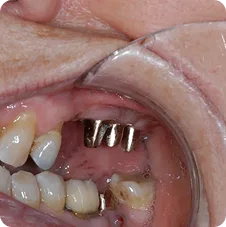

Post-operative Implant Placements

Impressions #18, 19 and 20

Impressions #30 and 31

Impressions for Crowns #13, 14, 15, 16 and 18

Crowns before placement

Crown Placements